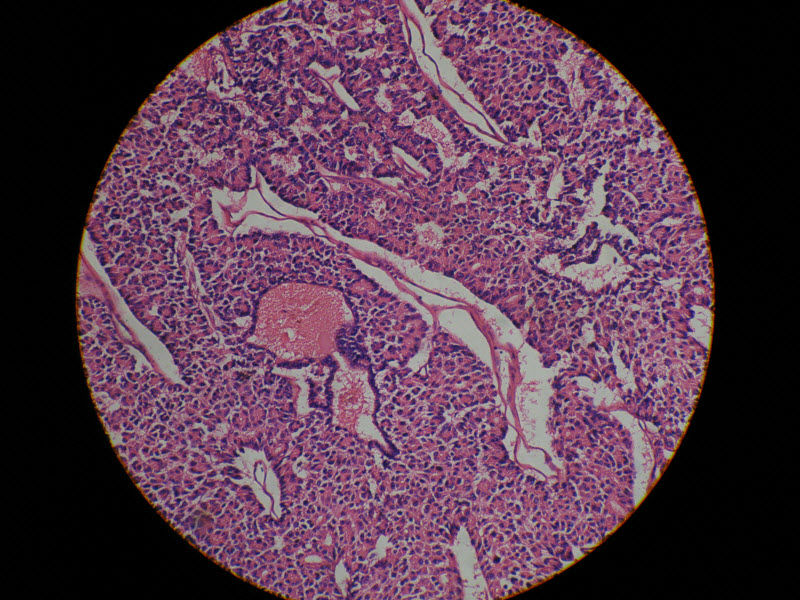

肾脏肿瘤,请教诊断!图2

名称:图2

描述:10倍

肾脏肿瘤,请教诊断!图3

名称:图3

描述:20倍